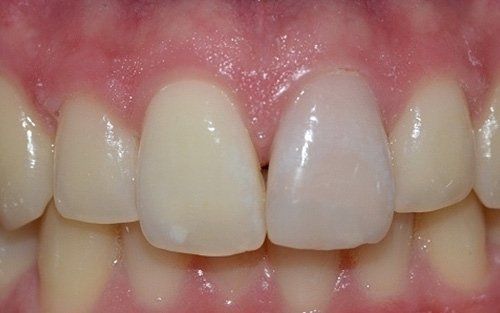

I denti da latte traumatizzati più spesso vanno incontro a necrosi con conseguente cambiamento di colore, divenendo grigiastri, segno della morte delle cellule della polpa dentaria. In altre occasioni, il dente può fratturarsi in maniera più o meno ampia: se il frammento viene ritrovato, potrà essere re-incollato in maniera invisibile, oppure verrà ricostruito con i materiali compositi.